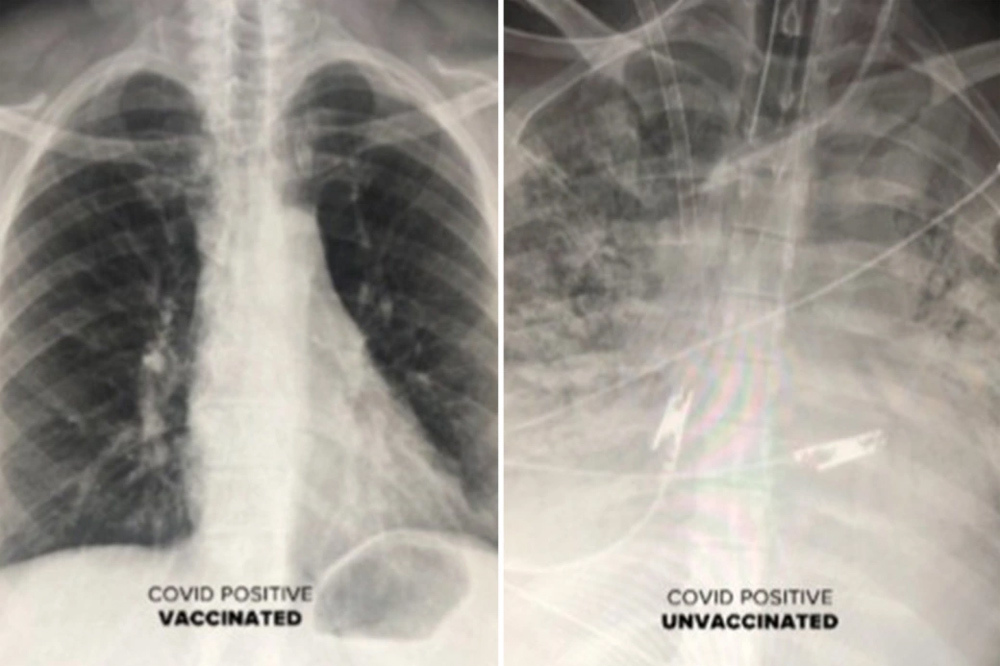

Bác sĩ Durrani cho biết, phim chụp phổi của những bệnh nhân Covid-19 từng được tiêm chủng cho thấy không khí lưu thông nhiều hơn. Trên hình, phần lớn phổi có màu đen, nghĩa là có rất ít hoặc không có tổn thương nào.

Ngược lại, phim chụp của một người không được tiêm chủng cho thấy phổi bị tắc nghẽn, hạn chế lưu lượng oxy đi khắp cơ thể.

Phim chụp phổi của người đã tiêm vắc xin (trái) không bị trắng xóa như người chưa tiêm vắc xin

Với hình ảnh cho thấy sự tàn phá mà virus SARS-CoV-2 có thể gây ra trong phổi, Tiến sĩ Durrani khẳng định: “Vắc xin đang hoạt động cực kỳ hiệu quả và ngăn không cho virus gây ra viêm phổi hoặc xâm nhập vào phổi”.